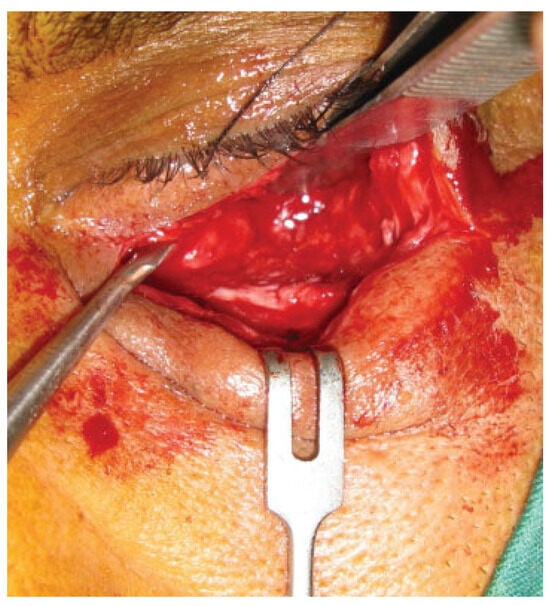

In this prospective study different parameters using biode-gradable plates for reconstruction of the blow-out fractures were assessed. The study was approved by the research committee of the medical ethics group of Shiraz University of Medical Sciences. The study sample was derived from the patients who referred to the Department of Craniomaxillo-facial Surgery for evaluation and management of orbital fracture between January 2009 and December 2010. Patients eligible for study inclusion had an impure blow-out fracture and there was a need to repair orbital floor and to fix the zygomaticomaxillary complex in a proper position. Patients who had pure blow-out fracture or minimal bone displace-ment in computed tomography (CT) scan views without the enophthalmos or the diplopia were excluded from the study. All the patients had a recent trauma and subsequently surgi-cal intervention was made between 1 and 10 days. A consul-tation was made with ophthalmologist before the surgical intervention. An axial and coronal CT scans were taken through 2-mm cuts for each patient before surgical interven-tion, immediate, and 18 months after surgery (Figure 1 and Figure 2). The amount of the orbital floor defect was measured in each case through CT scan. The surgical approach consisted of mid-lower incision for accessing the orbital rim and floor. Bone reduction and reconstruction was made through biode-gradable plate (PG910/PDO) (Figure 3). Titanium miniplates and screws were used for fixation of fractured infraorbital rim. The thickness of the biodegradable plates (PG910/PDO) was 0.5 mm. All the patients underwent secondary interven-tion to remove the titanium miniplates after 18 months. The orbital floor was reevaluated during the secondary interven-tion. The evaluation of remnant defects and biodegradable plates (complete or partial resorption) was made for every patient (Figure 4).

Figure 3. Image demonstrates placing a biodegradable plate on the orbital floor.